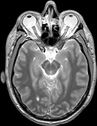

Visible Human male: Sectio transversalis 1107

CT

NMR

Pd T1 T2